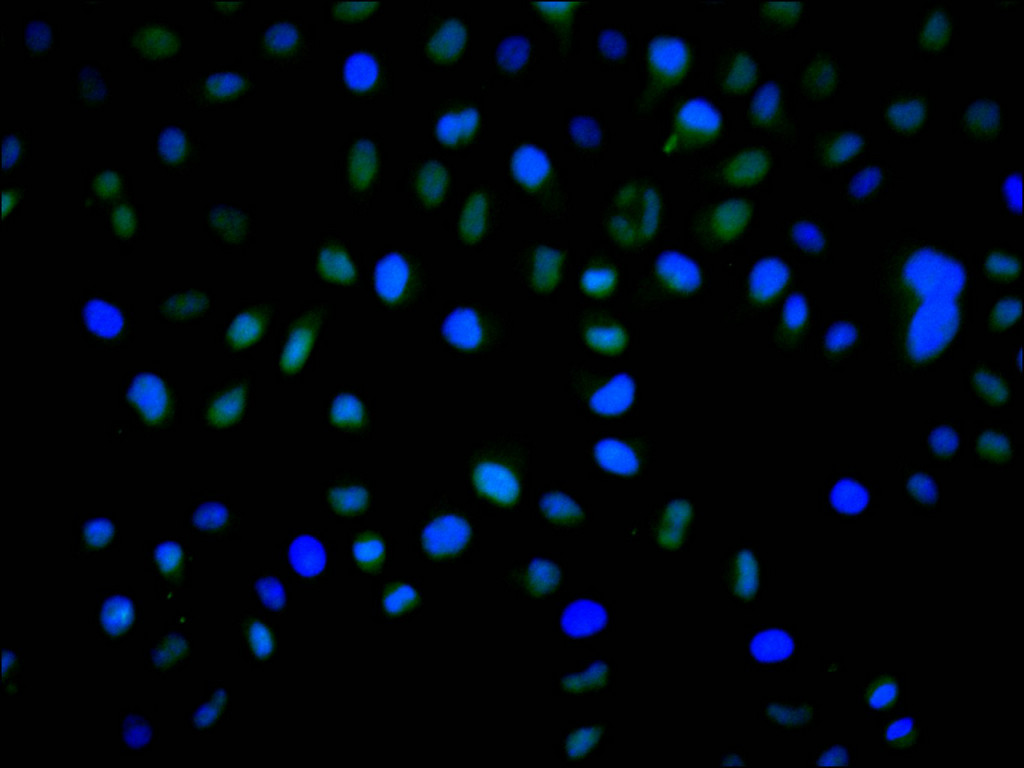

Immunofluorescence staining of Hela cell with CSB-RA580897A0HU at 1:50, counter-stained with DAPI. The cells were fixed in 4% formaldehyde, permeabilized using 0.2% Triton X-100 and blocked in 10% normal Goat Serum. The cells were then incubated with the antibody overnight at 4°C. The secondary antibody was Alexa Fluor 488-congugated AffiniPure Goat Anti-Rabbit IgG(H+L).